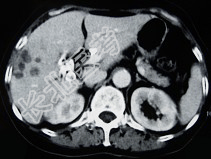

- 单项选择题女,66岁, 右上腹痛,发热伴有黄疸两月余, 消瘦、纳差,影像检查如图, 最可能的诊断为( )

A、胆囊癌及原发性肝癌

B、肝内胆管细胞癌

C、胆囊结石及脂肪肝

D、胆囊结石及肝血管瘤

E、胆囊癌肝转移